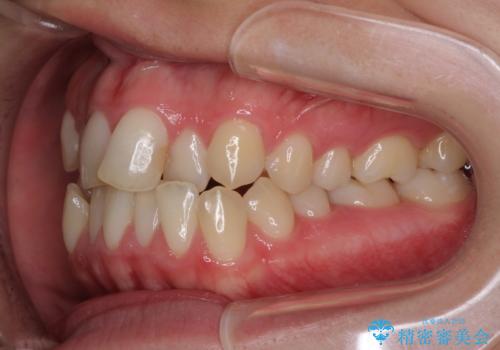

- 前歯のデコボコとクロスバイトを治したいとのことで来院された患者様です。

上下顎ともに歯列全体の側方拡大とIPR(歯と歯の間を削る)によってデコボコとクロスバイトが解消するように設計し、インビザラインにより治療を行うこととしました。

下顎骨の左側への骨格的なずれが強く、上下の正中の位置合わせや奥歯の咬み合わせ構築に苦労しました。